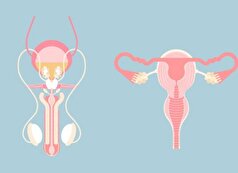

سن بالا یکی از عوامل سقط جنین!

به گزارش مجله خبری نگار، ملیحه عرب، به برخی از دلایل بروز سقط جنین پرداخت و افزود: عوامل زیادی میتواند باعث به روز سقط جنین شود.

وی گفت: سن بالای پدر، سابقه قبلی سقط، بیماریهای غدد از جمله دیابت و تیروئید به صورت کم کاری یا پر کاری، بیماریهای قلبی عروقی و فشارخون و هر بیماری طبی که روی سلامت مادر اثر بگذارد، مثل عفونتها؛ از دیگر علل سقط جنین است.

این متخصص زنان و زایمان، استرسهای مزمن را از دیگر عوامل کاهش سطح ایمنی بدن و تشدید کننده سقط جنین عنوان کرد و ادامه داد: به طور مثال استرس مزمن، جداییهای عاطفی، سو تغذیه و احساس نامنی در شرایط خاص مانند جنگ نیز میتواند خطر سقط جنین را افزایش دهد.

وی گفت: بارداری با iud گرچه نادر است، ولی ادامه حاملگی با iud خطر سقط را بالا میبرد. در عین حال استفاده از برخی داروها خطر سقط جنین را بالا میبرد بنابراین برای استفاده از هر دارو یا واکسنی در زنان باردار باید با پزشک مشورت شود.

مصرف داروهای مخدر یکی دیگر از علل تهدید کننده بارداری است که این استاد دانشگاه آن را مورد توجه قرار داد و افزود: مواد مخدر مثل کوکائین و متامفتامینها احتمال سقط را افزایش میدهند.

وی با اشاره به اینکه استفاده از سیگار، قهوه، و الکل خطر سقط را بالامی برد، تاکید کرد: این خطر به میزان مصرف نیز وابسته است.

عرب ادامه داد: عوامل محیطی مثل آلایندهها نظیر سرب، آرسنیک، آلودگی هوا، تماس با اشعه رادیاسیون و شیفتهای شبانه و نوع کار نیز میتواند در بروز سقط جنین اثرگذار باشد.

وی با بیان این موضوع که خطر سقط در سیاهپوستان و رنگین پوستان بیش از افراد سفید پوست است، تاکید کرد: ممکن است عواملی مانند استرس و شرایط اجتماعی و شغلی متفاوت در این گروه موجب افزایش خطر سقط جنین باشد.

به گفته عضو هیئت علمی دانشگاه علوم پزشکی شهید بهشتی، خونریزی یا هماتوم پشت جفت نیز از دیگر عوامل بروز خطر سقط جنین است.

عرب با بیان اینکه لیست مفصلی از عوامل افزایش خطر سقط جنین وجود دارد، افزود: باید توجه داشته باشیم که این موارد فقط احتمال افزایش سقط را بالا میبرد و به طور کلی نمیتوان تمام این موارد را دلیل اصلی سقط جنین دانست.

وی در ادامه به برخی از راههای اصلی پیشگیری از سقط جنین اشاره کرد و گفت: برای پاسخ به این سوال باید به علل بروز سقط جنین توجه داشته باشیم. میتوان سن بارداری را به زیر ۳۵ سال کاهش دارد ولی به این معنی نیست که در سنین بالای ۳۵ سال بارداری سالم نداریم.

عرب توصیه کرد: اگر سابقه سقط قبلی وجود دارد، میتوان با مصرف آسپیرین با دوز کم یعنی ۸۰ میلی در روز احتمال آن را کم کرد ضمن این که مصرف آسپیرین به همه افراد توصیه نمیشود.

وی با بیان اینکه در افرادی که دیابت دارند از هر نوعی که باشد با کنترل قندخون از قبل بارداری میتوان احتمال سقط را کم کرد، ادامه داد: در مبتلایان به بیماریهای تیروئید نیز چه کم کاری و چه پر کاری کنترل آن برای پیشگیری از سقط جنین توصیه میشود.

عرب با بیان اینکه بیماریهای قلبی عروقی، فشار خون یا هر بیماری در مادر باید کنترل شوند تا احتمال سقط کاهش یابد، افزود: اگر شرایط استرس مزمن وجود دارد میتوان بارداری را به تعویق انداخت و یا اگر چنانچه بارداری با iud رخ بدهد در اولین فرصت برای خروج iud مراجعه شود که احتمال سقط کاهش یابد چرا که در ماههای بالاتر حاملگی ممکن است دیگر نتوان iud را خارج کرد.

وی گفت: باید به مسائل طبی پدری نیز پیش از بارداری توجه شود و در صورت لزوم حاملگی به تعویق انداخته شود.

عرب با تاکید بر اینکه باید از تأثیر داروهای مصرفی در بارداری غافل نشد، ادامه داد: البته قطع بعضی از داروها در حاملگی میتواند خطرناک باشد و مادر باردار نباید سرخود اقدام به این کار بکند.

قطع مصرف سیگار و الکل و قهوه، قبل و حوالی بارداری از دیگر مواردی بود که این متخصص زنان و زایمان، به آن اشاره کرد و افزود: قطع مصرف مواد مخدر در بارداری از نظر سقط و اثرات سو دیگر بر بارداری توصیه میشود و البته میتوان قطع مصرف این مواد را با داروهای کمکی قطع مواد انجام داد.

وی ادامه داد: برای کاهش خطر سقط در حوالی بارداری از تماس با توکسینها و اشعه رادیاسیون باید اجتناب شود، همچنین در مورد آلودگی هوا شاید استفاده از ماسک یا کاهش تردد در مناطق خیلی آلوده را بتوان توصیه کرد.

کاهش و یا به طور قطع تغییر در روند شیفتهای شبانه در بارداری، توصیه دیگر این عضو هیئت علمی دانشگاه بود.

این متخصص زنان و زایمان ادامه داد: در موارد خونریزی و هماتوم در بارداری نیز مصرف داروهای خاص برای کاهش احتمال سقط توصیه میشود.

وی با تاکید بر اینکه رابطه جنسی در دوران بارداری با سقط جنین در ارتباط است، توضیح داد: در مایع منی موادی بنام پروستاگلاندینها وجود دارد که محرک انقباضات رحمی هستند بنابراین وارد نشدن مایع منی در بدن در زمان مقاربت با استفاده از کاندوم یا روش خارج نمودن در بارداری توصیه میشود.

این متخصص زنان و زایمان افزود: تماس جنسی حتی به طور کاملاً طبیعی ممنوع نیست و میتوان در صورت بروز انقباضات آن را تعدیل کرد ولی تماسهای خشن جنسی با افزایش احتمال سقط همراه است.

وی در پایان گفت: در موارد لکه بینی و خونریزی در بارداری توصیه میشود که تماس جنسی تا مدتی قطع شود.

- علائم ناباروری در زنان و مردان!